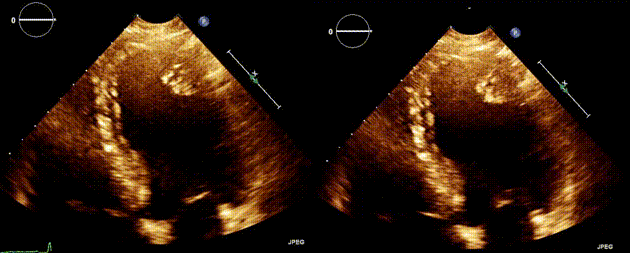

患者,男性,49 岁,因心脏杂音行经胸超声心动图检查,发现心尖部外侧段心腔内壁有一 2 × 2 cm 的强回声团块,考虑为心内肿物,可能为肿瘤,伴或不伴表面血栓。未发现局部室壁运动异常,左心室射血分数为 55%(图 A,视频 S1)。

图A 经胸超声心动图(心尖四腔心切面)显示心尖部外侧段存在强回声团块,看似血栓